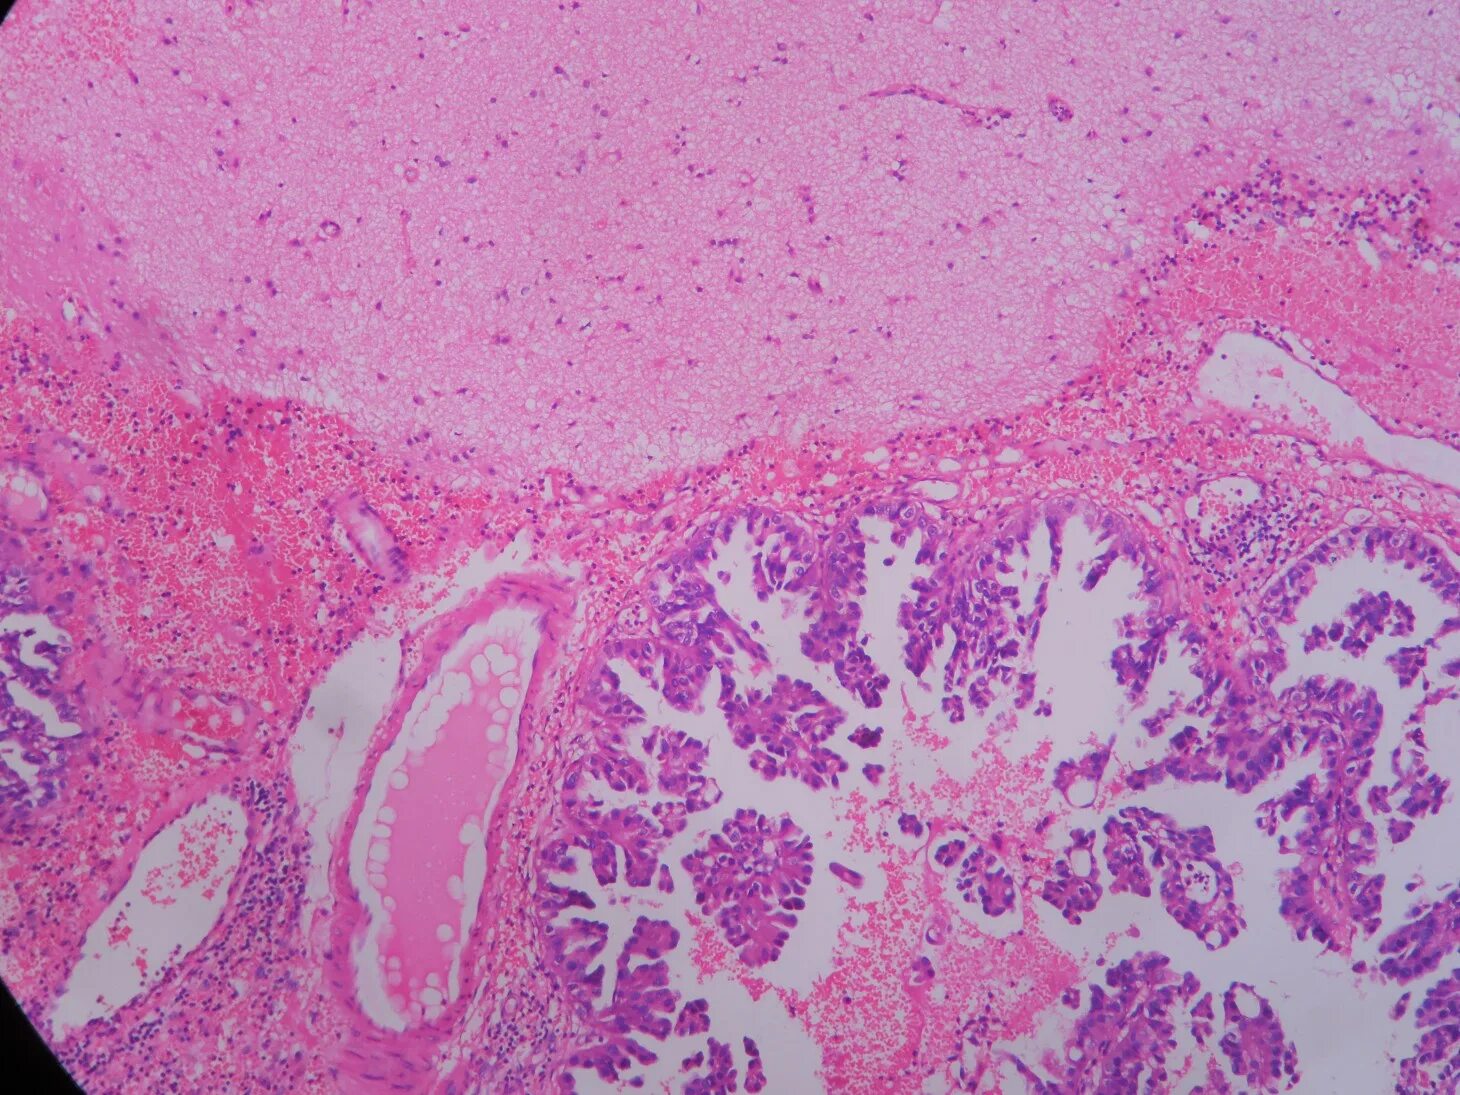

Гистология слизистой